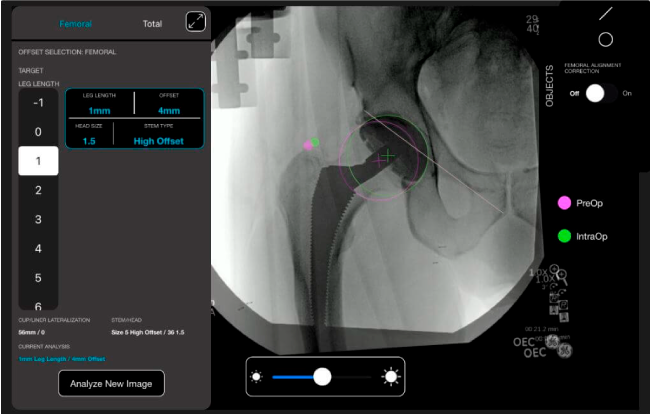

Planeación preoperatoria mediante la creación de plantillas digitales para reemplazo de cadera y análisis intraoperatorio

Favorece la restauración biomecánica del offset femoral.

Desplazamiento y offset para posicionamiento óptimo del componente (vástago) femoral.

Con tecnología ONETRIAL® que calcula automáticamente el cambio en la longitud de la pierna y el desplazamiento para todas las combinaciones de implantes en una tabla fácil de leer.